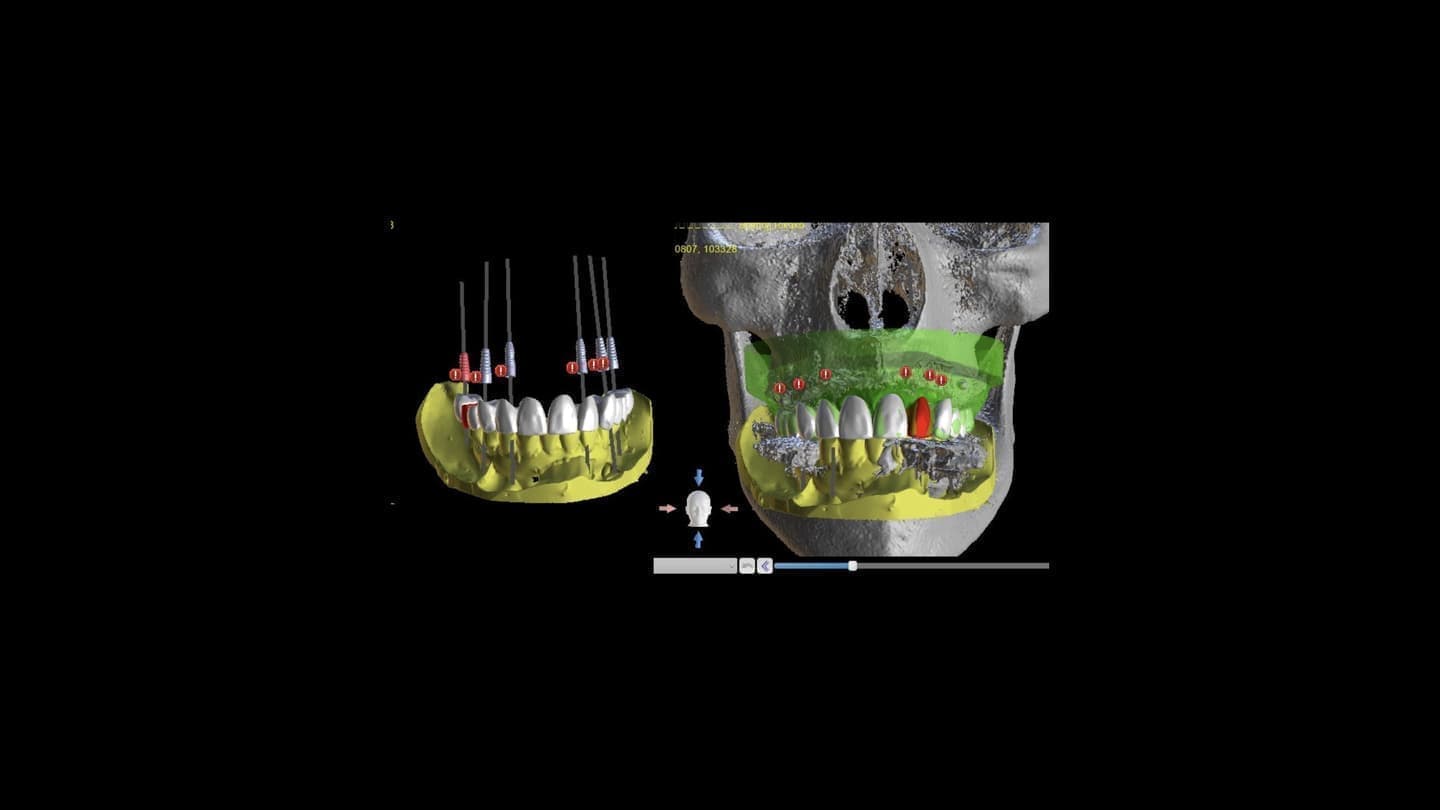

インプラント治療

CT診断、CAD/CAMを活用した最先端の治療を行います

シュミレーションした場所に確実にインプラントを設置していきます

コンピューター診断

手術時の「人為的なミス」を最小限に抑えることができる